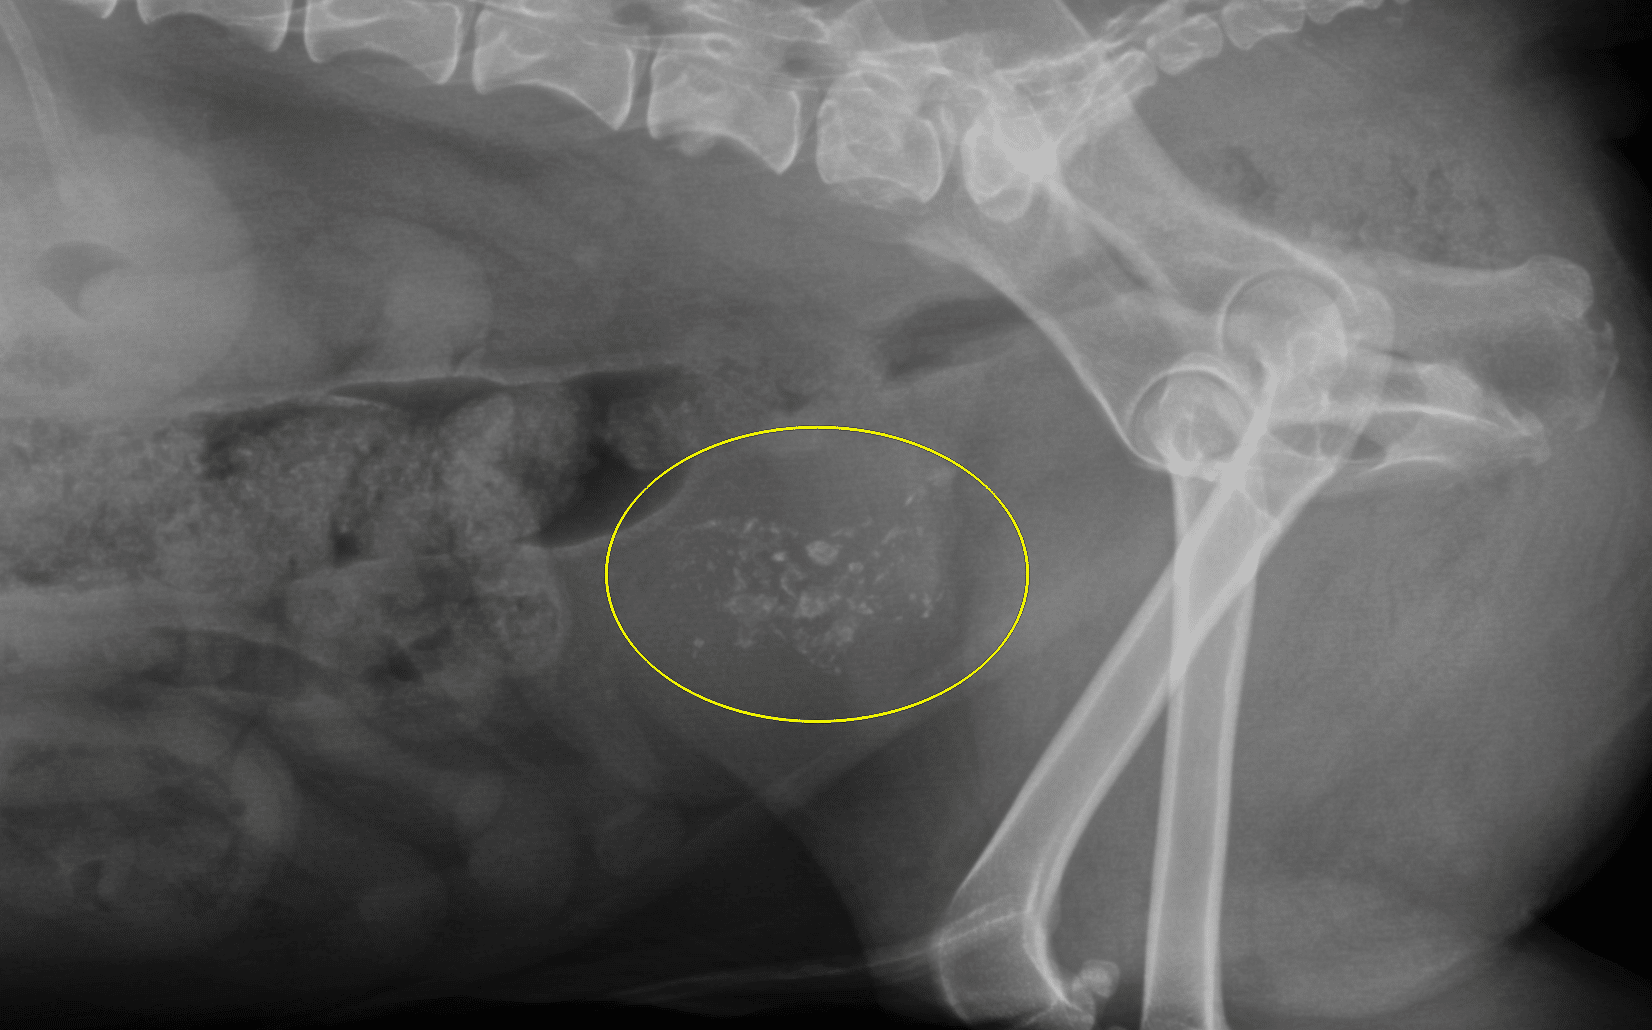

The overwhelming majority of cancerous bladder lesions are transitional cell carcinoma (TCC). While squamous cell carcinoma, adenocarcinoma, and various soft tissue sarcomas are also reported, in my experience, these are vanishingly rare. TCC most commonly arises from the region of the trigone, along the dorsal aspect of the bladder neck. However, it can arise from anywhere along the mucosal surface of the lower urinary tract. Mineralization significantly raises the degree of concern for malignancy. Radiographically, most bladder mass lesions are not detectable unless they are mineralized, since fluid and soft tissue have the same opacity. (Figure 4)

Figure 4: Lateral radiograph in a patient with a large mineralized bladder transitional cell carcinoma (yellow circle). Note the irregular shapes of the mineral opacities, which are more typical of dystrophic mineralization rather than urolithiasis. Ultrasound or CT is generally necessary to differentiate a mineralized mass from urolithiasis, however.